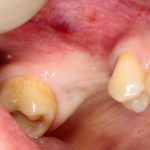

Но, если мы говорим не о поиске истины, а о выборе метода лечения? К примеру, мы столкнулись с распространенной ситуацией:

или вот:

когда атрофия альвеолярного гребня препятствует установке правильных имплантатов в правильное положение (см. Рекомендации по установке имплантов. Часть V).